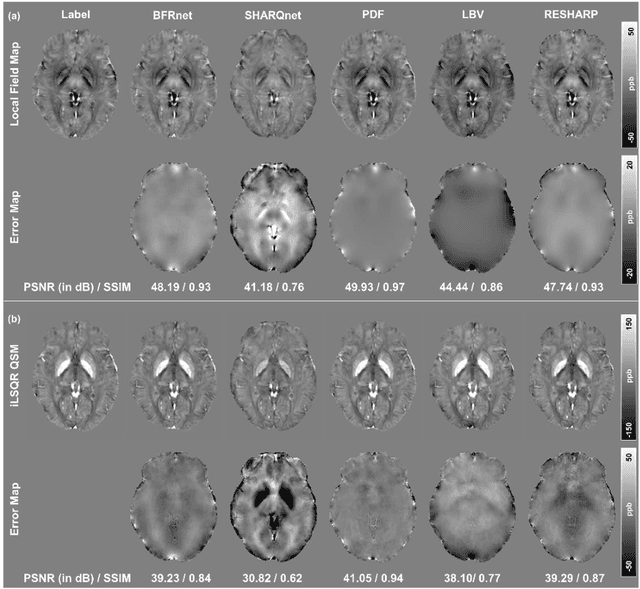

Abstract:Introduction: Background field removal (BFR) is a critical step required for successful quantitative susceptibility mapping (QSM). However, eliminating the background field in brains containing significant susceptibility sources, such as intracranial hemorrhages, is challenging due to the relatively large scale of the field induced by these pathological susceptibility sources. Method: This study proposes a new deep learning-based method, BFRnet, to remove background field in healthy and hemorrhagic subjects. The network is built with the dual-frequency octave convolutions on the U-net architecture, trained with synthetic field maps containing significant susceptibility sources. The BFRnet method is compared with three conventional BFR methods and one previous deep learning method using simulated and in vivo brains from 4 healthy and 2 hemorrhagic subjects. Robustness against acquisition field-of-view (FOV) orientation and brain masking are also investigated. Results: For both simulation and in vivo experiments, BFRnet led to the best visually appealing results in the local field and QSM results with the minimum contrast loss and the most accurate hemorrhage susceptibility measurements among all five methods. In addition, BFRnet produced the most consistent local field and susceptibility maps between different sizes of brain masks, while conventional methods depend drastically on precise brain extraction and further brain edge erosions. It is also observed that BFRnet performed the best among all BFR methods for acquisition FOVs oblique to the main magnetic field. Conclusion: The proposed BFRnet improved the accuracy of local field reconstruction in the hemorrhagic subjects compared with conventional BFR algorithms. The BFRnet method was effective for acquisitions of titled orientations and retained whole brains without edge erosion as often required by traditional BFR methods.